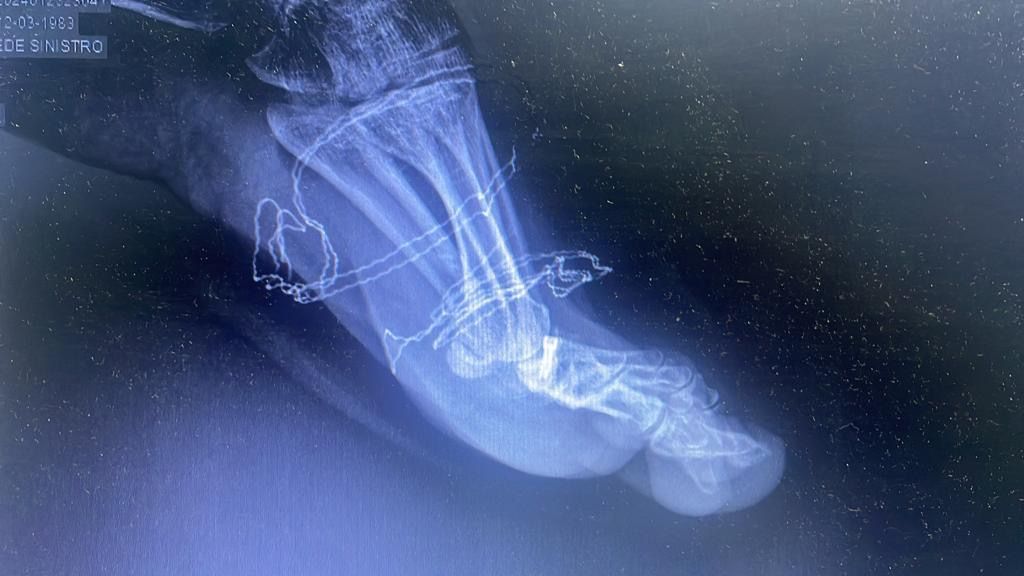

L’intervento per la correzione del piede piatto prevede un ricovero di un giorno (Day Surgery), viene eseguito in anestesia locale e prevede l’inserimento di una piccola vite nel seno del tarso.